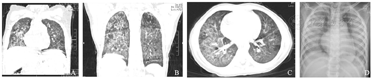

见表1。7例患儿除肾病综合征患儿外均有应用口服复方磺胺甲口,恶唑(TMP-SMX)预防PCP治疗史,其中4例患儿自行停药2~4周发生PCP;另2例一直口服TMP-SMX预防PCP患儿,其中1例存在CD4细胞显著下降,CD4细胞49/μL;所有患儿均有LDH[(745.7±317.0) U/L]和β-D-葡聚糖[(513.8±225.0)pg/mL]升高。影像学检查(图1):X线胸片表现为双肺弥漫性细小结节和网状影像,随病情进展出现双肺弥漫性高密度实变即"白肺";胸部CT显示双肺弥漫性间质性改变伴肺内多发渗出,表现为磨玻璃征,2例患儿可见弥漫网状影,1例患儿并发双侧气胸、纵隔气肿。

A、B、C :胸部CT显示双肺弥漫性间质性改变伴肺内多发渗出性病变;B:弥漫网状影;D:X线胸片表现为"白肺"。

影像学检查对于PCP的诊断非常重要,非HIV感染PCP典型的放射影像学特征为双肺弥漫性间质浸润,X线表现以双肺弥漫性、对称性细小结节和网状影像为主,CT检查通常可表现为磨玻璃征、肺气囊征、月牙征、支气管血管束长索条征等,以磨玻璃征最常见[14]。病变主要分布在肺门周围,随病情进展可向肺野周围发展,3~4 d后病变融合出现典型的肺泡渗出性病变特征,X线可表现为"白肺",此时应注意与其他肺泡填充性疾病如肺泡蛋白沉着症、弥漫性肺泡出血、急性肺水肿等相鉴别。